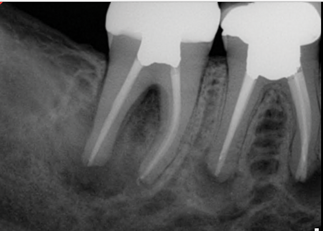

(5.) Preoperative radiograph of tooth No. 19 following a pulpectomy procedure that was complicated by an intraoperative furcal perforation.

Figure 5

(6.) Postoperative radiograph showing immediate perforation repair using MTA followed by complete obturation.

Figure 6